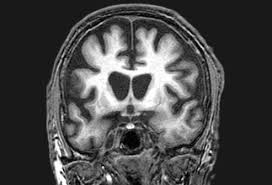

The Radiology Assistant Dementia Role Of Mri

The Radiology Assistant Dementia Role Of Mri from rad.desk.nl

Protein deposits, called lewy bodies, develop in nerve cells in the brain regions involved in thinking, memory and movement (motor control). It's rare in people under 65. Also, there is a helpline for support provided by dementia. Dementia with lewy bodies (dlb), also known as lewy body disease, is a neurodegenerative disease (a synucleinopathy to be specific) related to parkinson disease. Dementia with lewy bodies appears to be the second most common form of dementia, accounting for about one in five cases. Further research is needed to clarify the relationships among them. Some scans (ct and mri scans) look at how the different parts of the brain fit together, rather than how the parts work together. The deposits are called lewy bodies and are named after friedrich h. Dementia is the name for problems with mental abilities caused by gradual changes and damage in the brain. Lewy body dementia, also known as dementia with lewy bodies, is the second most common type of progressive dementia after alzheimer's disease dementia. Certain nuclear scans of the brain, including positron emission. This may include a magnetic resonance imaging (mri) or computed tomography (ct) scan of the brain. After alzheimer disease (ad), dementia with lewy bodies (dlb) is one of the most common types of degenerative dementia.